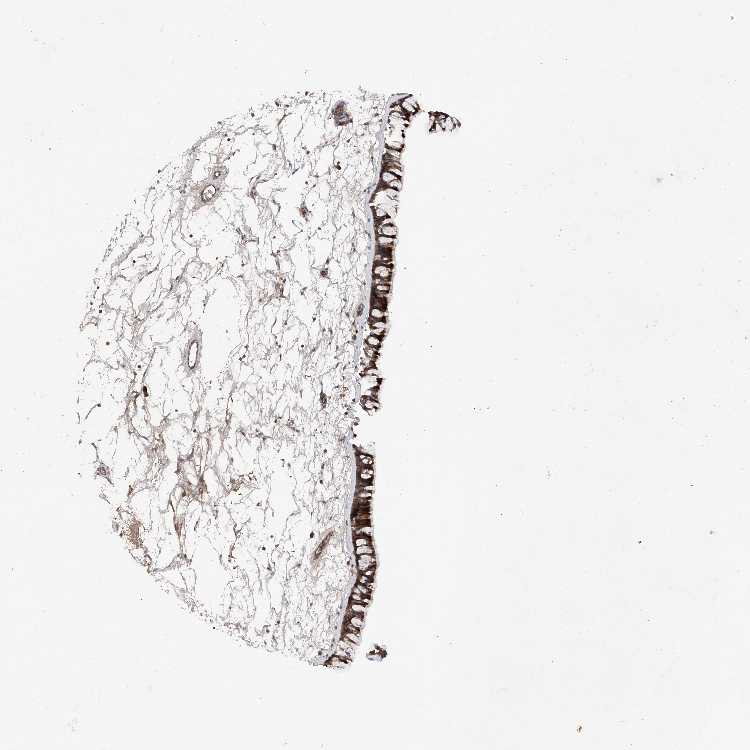

TISSUE PRIMARY DATA NASOPHARYNX Show tissue menu

NASOPHARYNX - Antibody stainingi

Antibody staining in the annotated cell types in the current human tissue is reported as not detected, low, medium, or high, based on conventional immunohistochemistry profiling in selected tissues. This score is based on the combination of the staining intensity and fraction of stained cells.

Each image is clickable and will lead to virtual microscopy that enables deeper exploration of all samples and also displays staining intensity scores, fraction scores and subcellular localization as well as patient and tissue information for each sample.

Antibody HPA028882

Respiratory epithelial cells High